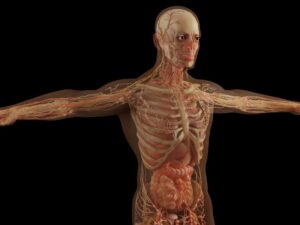

São os distúrbios dos nervos. Os nervos são estruturas finas e longas, de coloração esbranquiçada, especializadas em condução do estímulo neurológico central até um órgão

O quadril é a maior articulação do corpo humano e consequentemente uma infinidade de doenças pode acometer essa articulação, desde inflamações até fraturas. A junção